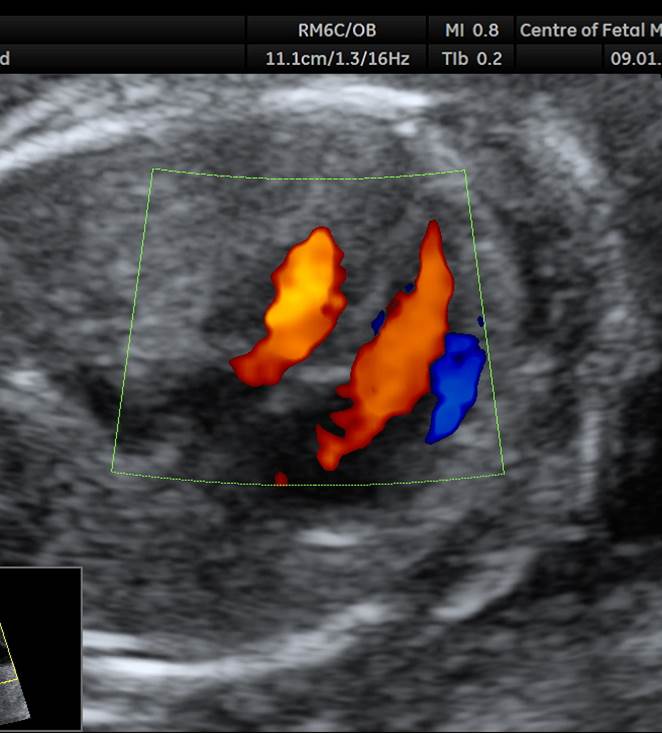

- У плода стеноз легочного ствола. На 4камерном срезе сердца обращает на себя внимание утолщение миокарда правого желудочка. В срезе через правый выходной отдел видно сужение легочного ствола на уровне клапана и постстенотическое расширение. В режиме ЦДК определяется антеградный турбулентный кровоток в легочном стволе.